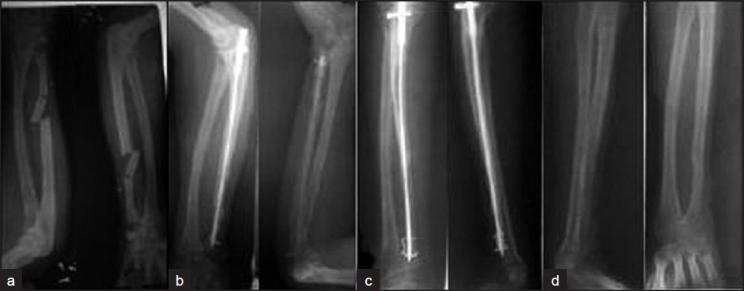

Lack of availability of interlocked nails made plate osteosynthesis the first choice of treatment of forearm fractures inspite of more surgical exposure, periosteal stripping and big skin incision subsequent scar along with higher risk of refracture on implant removal. We hereby report the first 12 cases with 19 forearm bone fractures internally fixed by indegenous interlocked nail.

Existing square nails were modified to have a broad proximal end of 5.5 mm with a hole for locking screw of 2.5 mm. The nail has a distal hole of 1/1.2/1.5 mm in 2.5/3/3.5 mm diameter nail, respectively. A new method of distal locking with a clip made of k wire is designed. The clip after insertion into the bone and hole in nail and opposite cortex snuggly fits the bone providing a secure locking system. Twelve skeletally mature patients, mean age 32 years (range 24-45 years) with 19 diaphyseal fractures of the forearm were treated with this indigenously made new nail. The patient were evaluated for fracture union, functional recovery and complications. The functional outcome was assessed by disabilities of arm, shoulder and hand questionnaire (DASH score).

RESULTS

Time to radiographic union ranged between 12 and 28 weeks, with a 100% union rate. Complications were minimal, with mild infection in open fracture (n=1) and delayed union (n=1) in patient with comminuted fracture of the ulna only. The clinical results were excellent. The DASH score ranged between 0 and 36 points.

This new interlocking nail may be considered as an alternative to plate osteosynthesis for fractures of the forearm in adults. The advantages are benefit of closed reduction, smaller residual scar, reduced cost and early union with allowance of immediate movements.